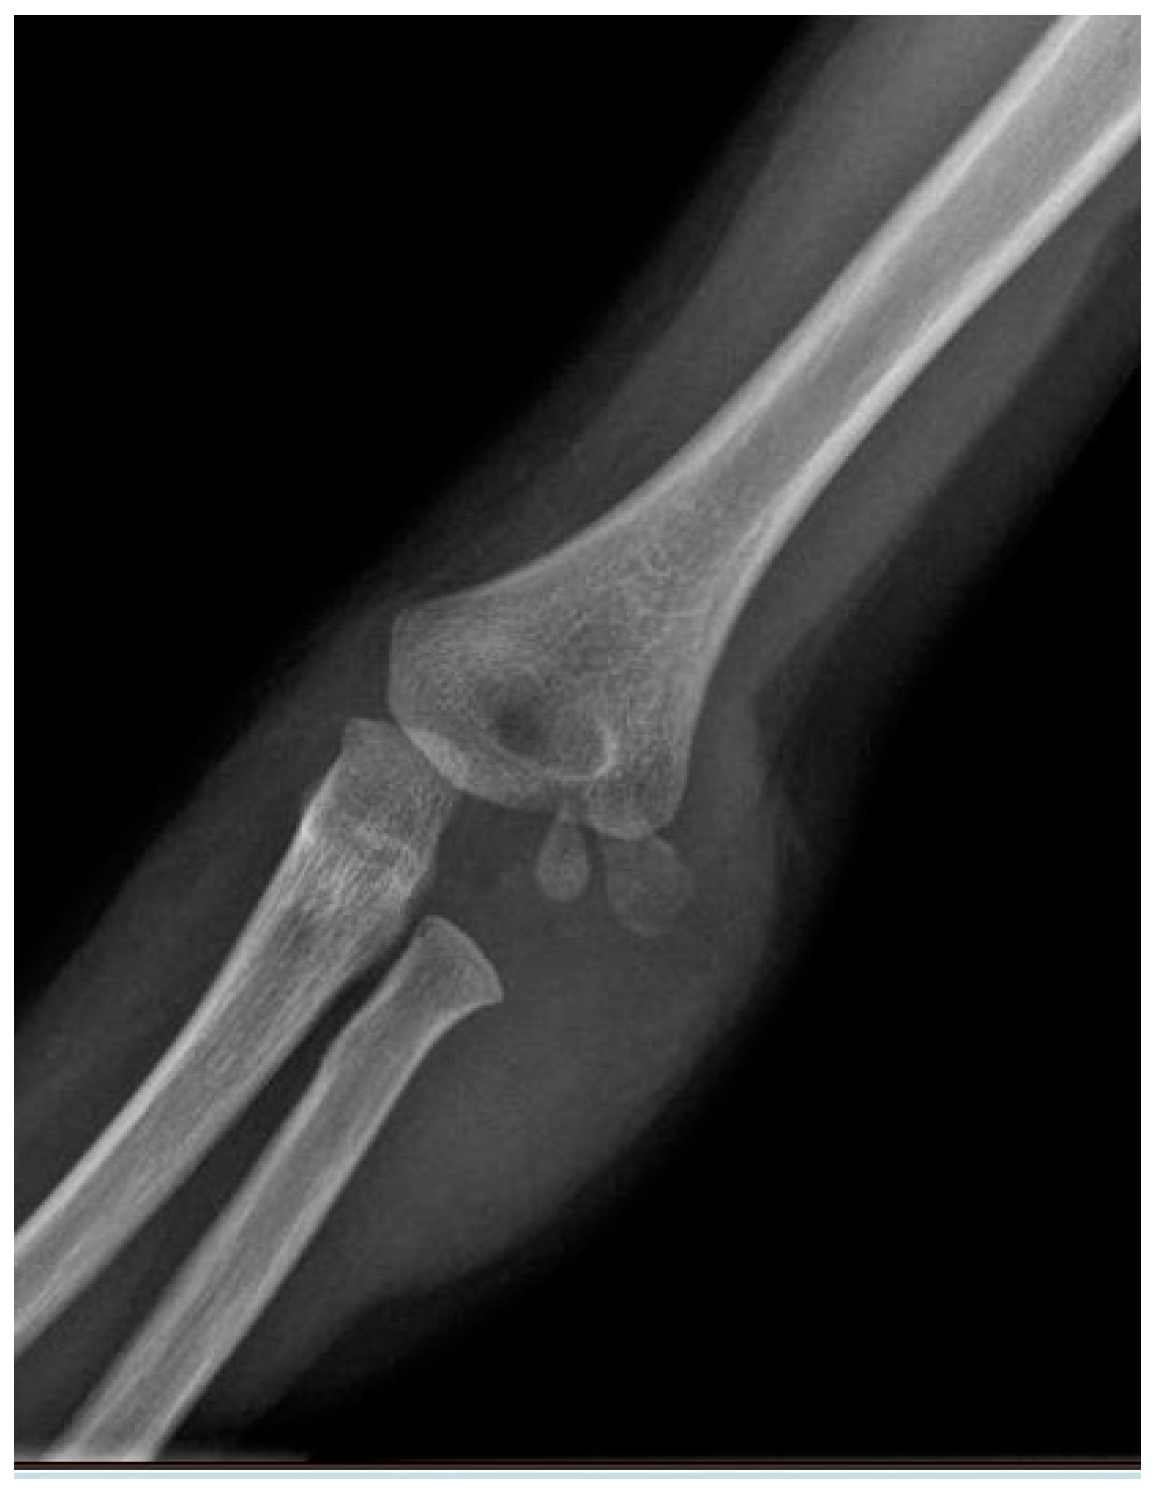

2. Materials and Methods

3. Results